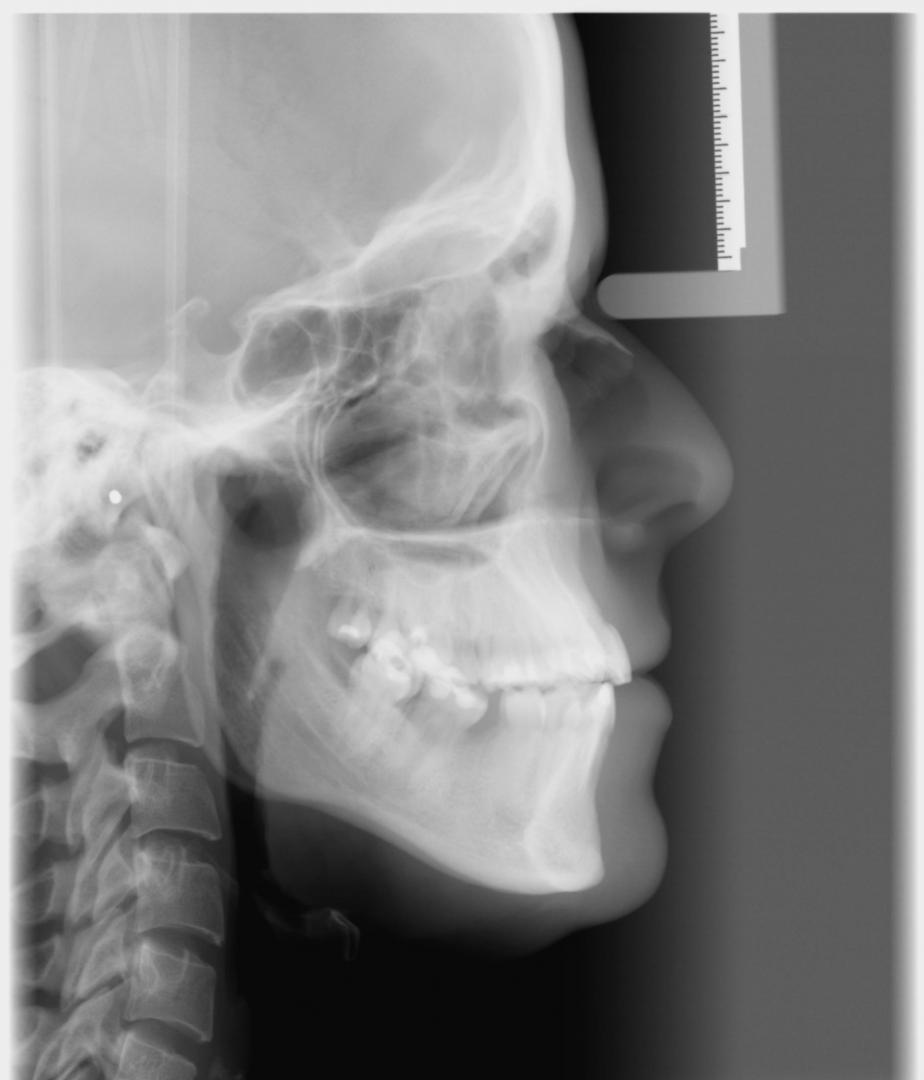

- Cephalometric image